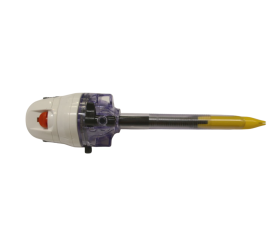

Sistema de Trombectomia AngioJet Medrad Possis 5000A

Console do Sistema de Trombectomia AngioJet Medrad Possis 5000A - Semi novo

O Sistema de Trombectomia AngioJet é um dispositivo de trombectomia periférico farmacomecânico com aspiração ativa e liberação lítica Power Pulse™ projetado para tratar a gama mais ampla de vasos com trombose, restaurando rapidamente o fluxo sanguíneo.

O sistema de Trombectomia AngioJet proporciona a potência e flexibilidade para remoção rápida de trombos, restauração rápida de fluxo sanguíneo, melhora de sintomas e facilidade de uso.

Modelo de console compacto e altamente móvel

Console AngioJet Ultra 5000A (Console ou Console AngioJet Ultra)

O Console é um dispositivo de uso múltiplo que controla o Conjunto de Trombectomia. Ele dirige

a bomba, regula a entrada e saída de fluido, fornece ao operador AngioJet

Prompts de configuração do sistema, volume total de solução salina infundida e mau funcionamento do sistema AngioJet

em formação. O console é ativado pressionando o pedal.

Visão Geral do Console

Console Avançado de Fácil Utilização

- Sistema de controle automatiza a configuração e monitora a operação

- Interface passo a passo para eficiência de procedimento

- Sistema automatizado se autoconfigura para cada cateter

- Console compacto e altamente móvel